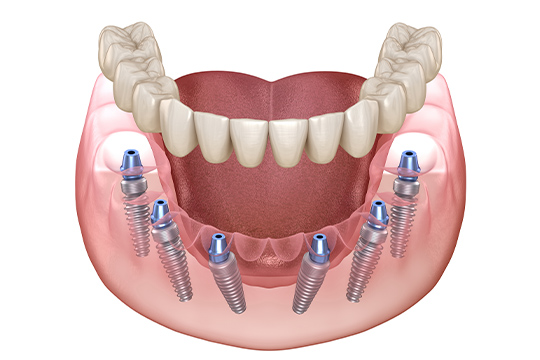

전악 임플란트는 임플란트 틀니보다 씹는 힘이 훨씬 좋습니다.

내 치아처럼 사용이 가능하며

전체 치아 기능의 90% 정도로 회복력이 좋습니다.

개인에게 맞는 계획으로 임플란트를 식립합니다.